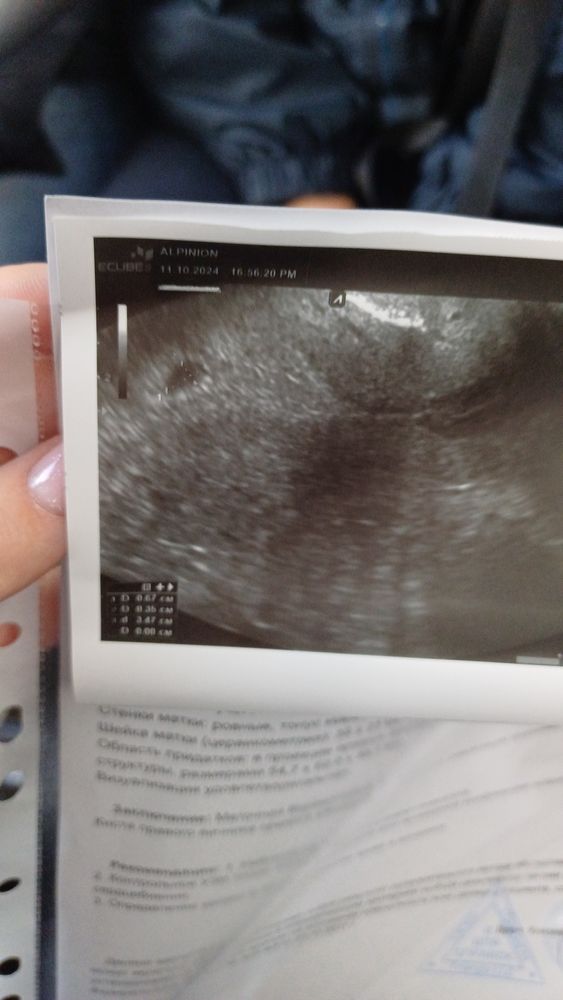

16дпп (узи!)

Так. Все у тебя отлично. Отставить панику. Вон уже 5 мм дом у человека!

Tanya, 5дпп-22, 7дпп-100, 9дпп-238, 11дпп-573, 13дпп-1360 Потому что я всегда хожу на узи с 14дпп)

Киста может как-то повлиять на плодное яйцо?

Elvirochka, да нет конечно) но она даже не сказала ЖТ это или какая киста. В среду переделаю у другой..

Elvirochka, не, я просто распаниковалась к тому, что попала на все такие же показатели, как в зб год назад🙈и меня переклинило ужасно. Щас смотрела узи с Мирой на 14дпп, Там пя было 4мм.